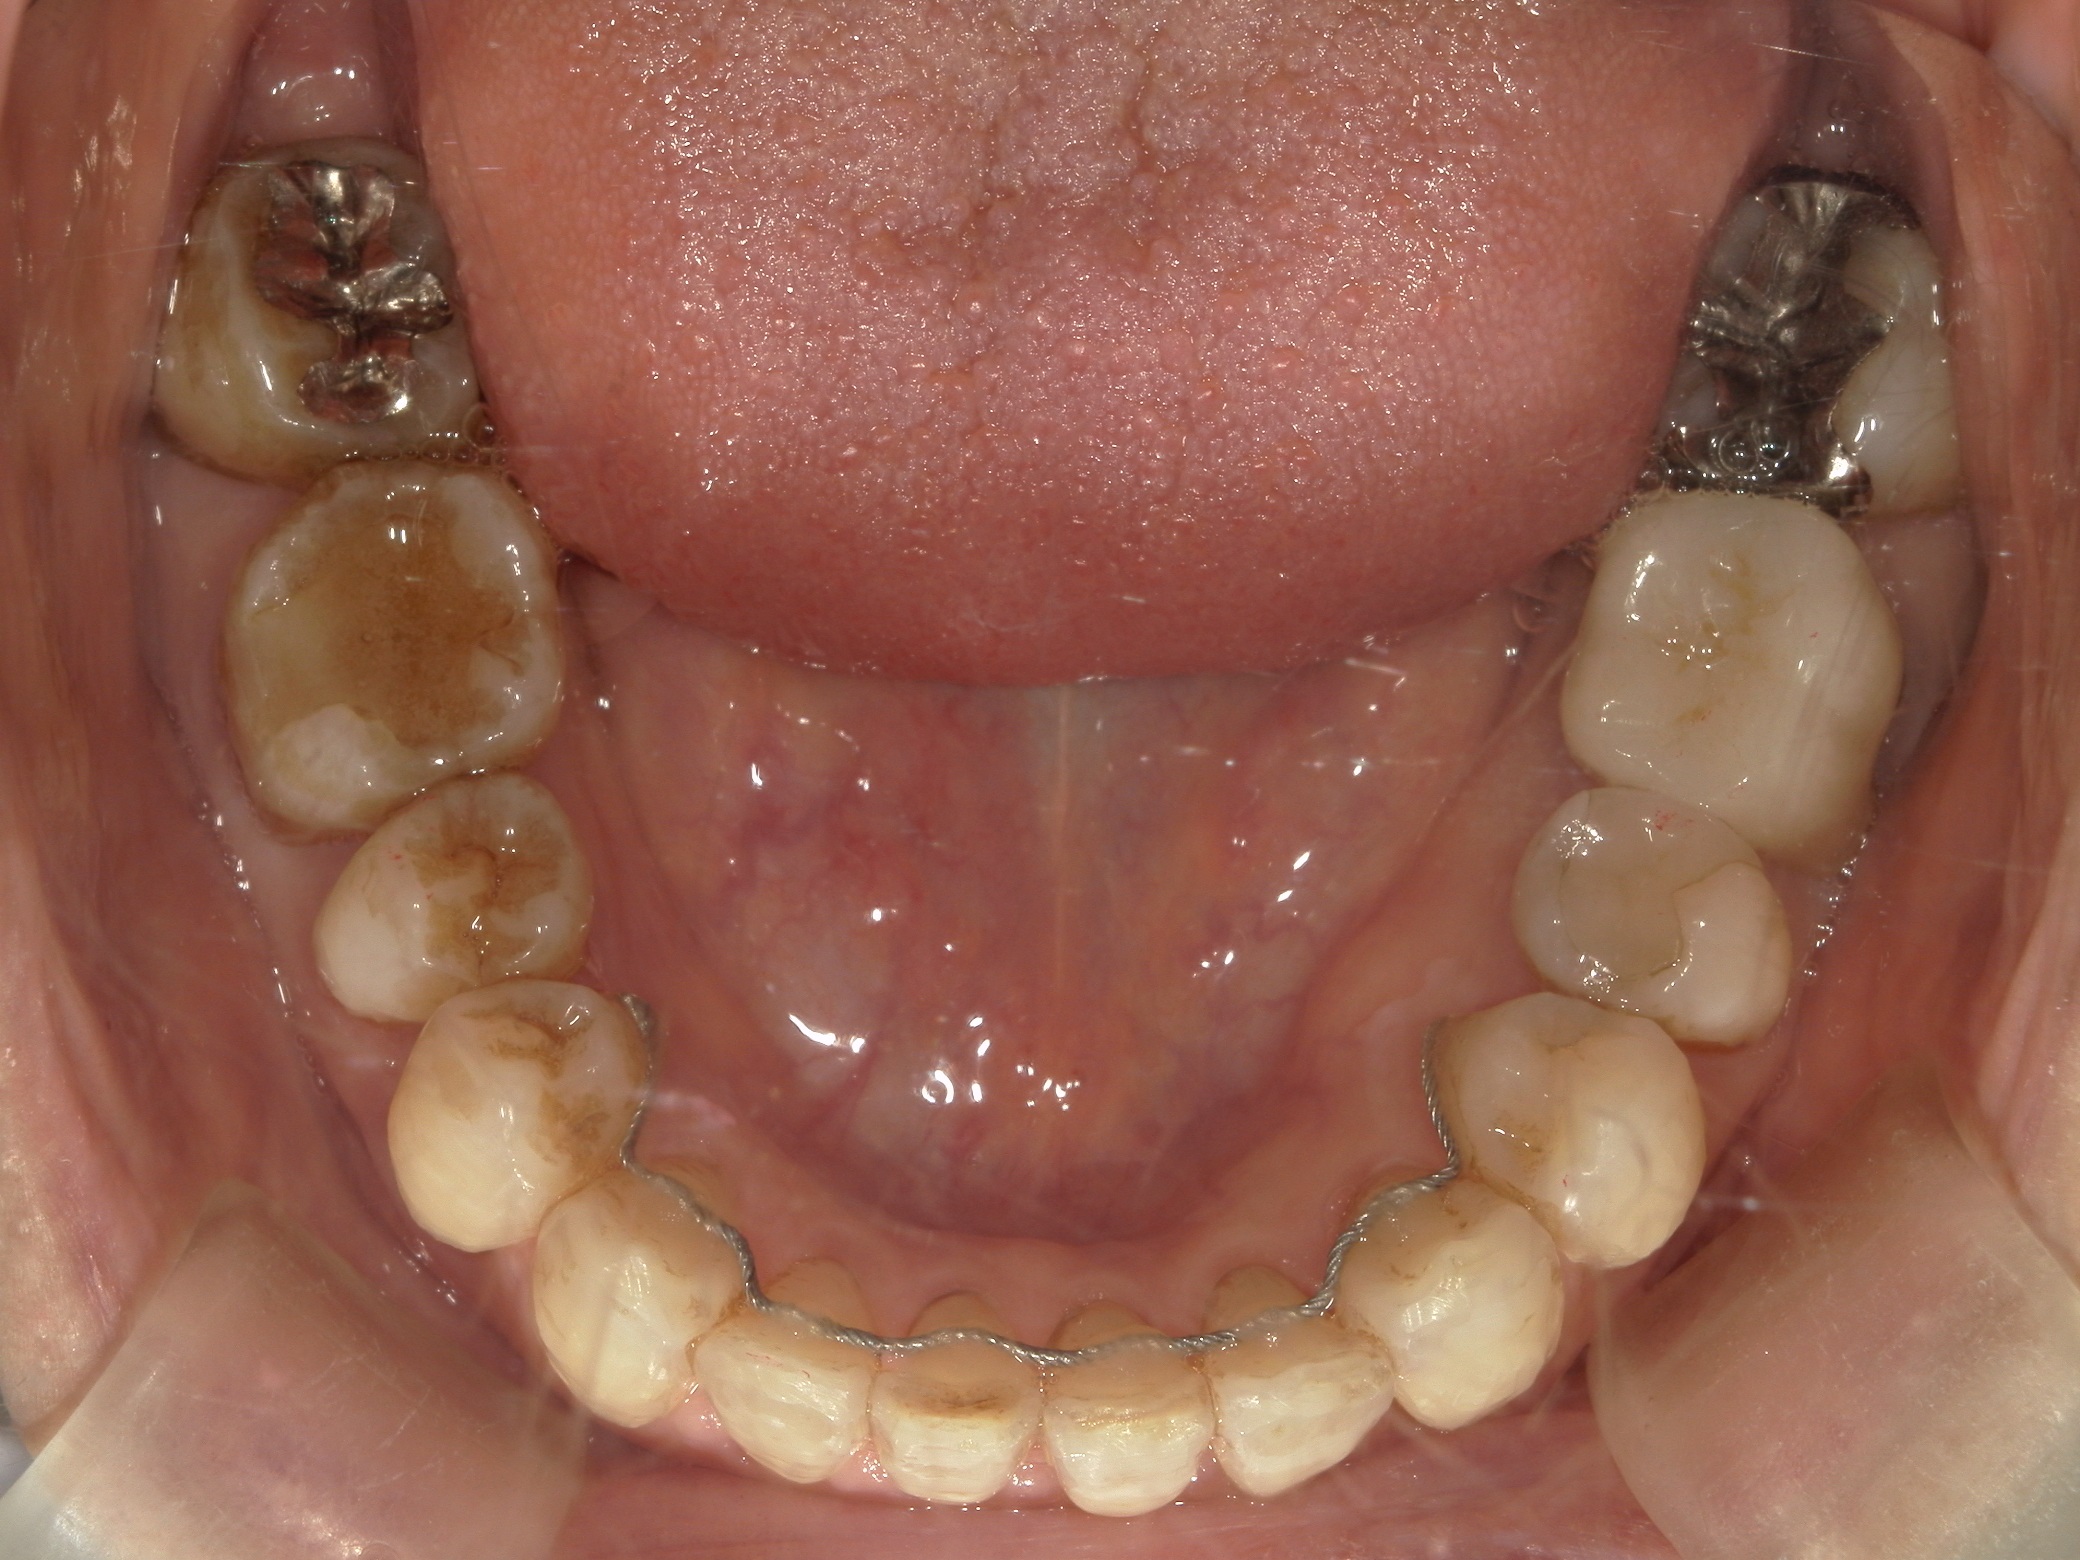

インビザライン矯正 症例(25)

スライスカットを併用。

カテゴリー : ガタガタ(叢生)